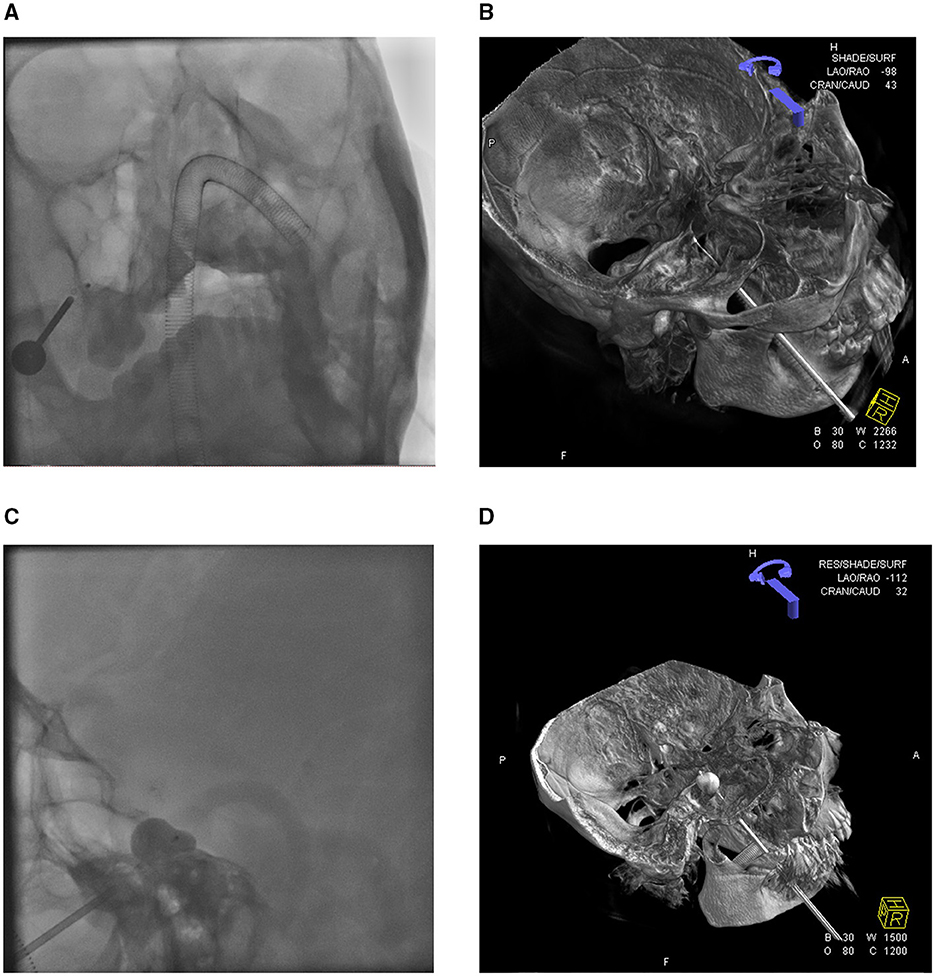

All 40 patients underwent endotracheal intubation under general intravenous anesthesia. The procedures were completed in all cases, with an average surgical duration of approximately 30 min. Bradycardia (heart rate <50 bpm) occurred in 38 patients during the insertion of the puncture needle sheath into the FO. Procedures were suspended when bradycardia occurred and resumed only after recovery to baseline heart rate (>70 bpm). For persistent bradycardia, atropine (0.5 mg) was administered intravenously before continuation. The procedure was immediately terminated and a precordial thump was applied in two patients who developed cardiac arrest. Cardiac rhythm was restored in both patients following electrocardiographic monitoring, with the subsequent resumption of standard surgical protocols, as shown in Figure 1 demonstrating intraoperative 3D DSA navigation.

Figure 1. 3D-DSA reconstruction displays the position of the balloon catheter. (A) Orthography shows the puncture needle and balloon catheter. (B) 3D-DSA visualization of balloon catheter placement status. (C) The lateral view of the balloon presented the classic “pear shape.” (D) 3D-DSA visualization of balloon dilation.